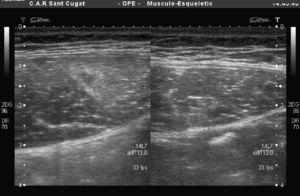

A pesar de los 7 días transcurridos, se observa una disrupción del correcto patrón fibrilar con sufusión hemática que invade la totalidad de la lesión y edema perilesional (figura 1, figura 2). El examen ecográfico también mostró una imagen fibrosa que, una vez interrogado el paciente, se concluyó que correspondía a una lesión antigua en el mismo vientre y asintomática en el momento de la consulta (figura 3).

Figura 1. Imagen ecográfica transversal de la lesión localizada en la zona próxima a la aponeurosis profunda a la derecha de la imagen.

Figura 2. Imagen ecográfica longitudinal de la misma ruptura.